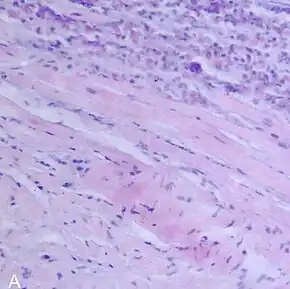

A microscope image of myocarditis at autopsy in a person with acute onset of heart failure